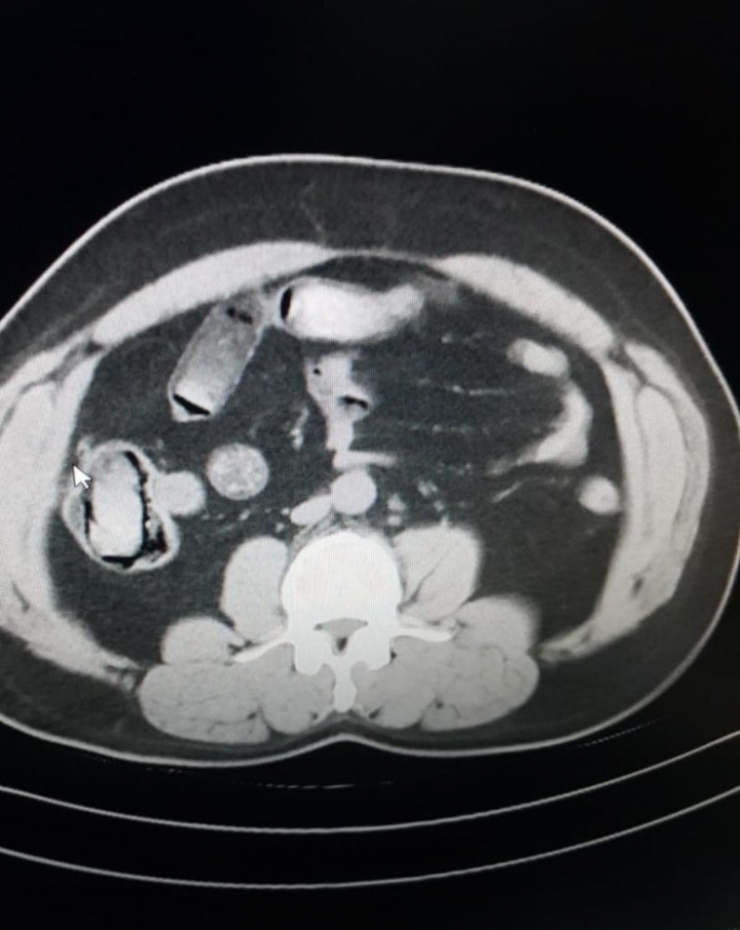

Geçtiğimiz hafta, İzmir Adnan Menderes Havalimanı'na gelen 5 İranlı yolcunun, şüphe üzerine kimlik bilgileri sorgulandı. Üst ve bagaj aramaları da yapılan yolcularda herhangi bir bulguya ulaşılamayan narkotik ekipleri, yolculardan birinin şüpheli tavırlar sergilemesi üzerine 5 İranlıyı röntgen çektirmek üzere hastaneye götürdü.

İran vatandaşı 5 şahsın üzerinde yapılan incelemelerde, midelerinde kapsül olduğu anlaşıldı. Kapsülleri istifra yoluyla çıkartılan İranlılardan toplam 298 kapsülde 3 kilo 385 gram eroin ele geçirildi.